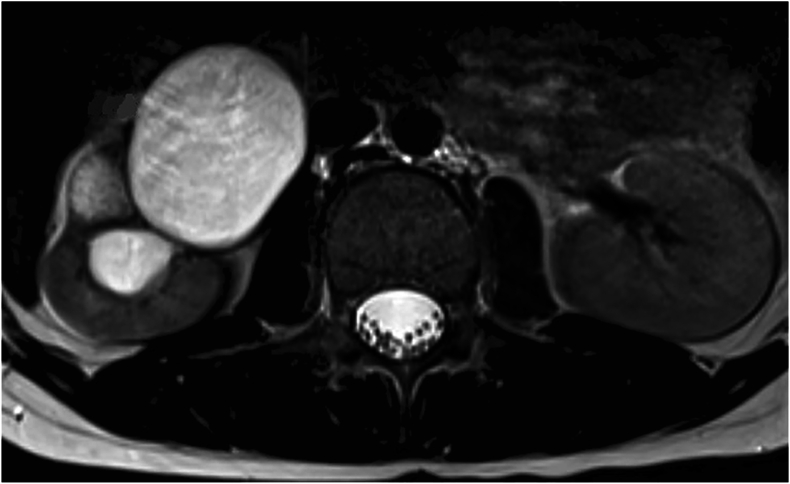

Results: The average age of the 1409 patients was 15.5 years (95% CI: 15.4, 15.6). Back pain (90.1%) was the most common reason for lumbar MRI. Thirty-five UFs were found in 33 patients (2.3%): 19 were spinal cord-related, 15 were peritoneal-related, and one was vascular. Eight peritoneal findings involved the kidneys: two atrophy, two hypoplasia, two renal cysts, one pelvic kidney, and one hydronephrosis. Five patients had a syrinx, and two had spine tumors. Out of 33 patients with UFs, 11 required a change in treatment plan (33.3%). Back pain was not associated with an increased risk of UF. Patients with an UF on MRI had 2.60 times higher odds of experiencing a change in treatment plan.

Abstract Image